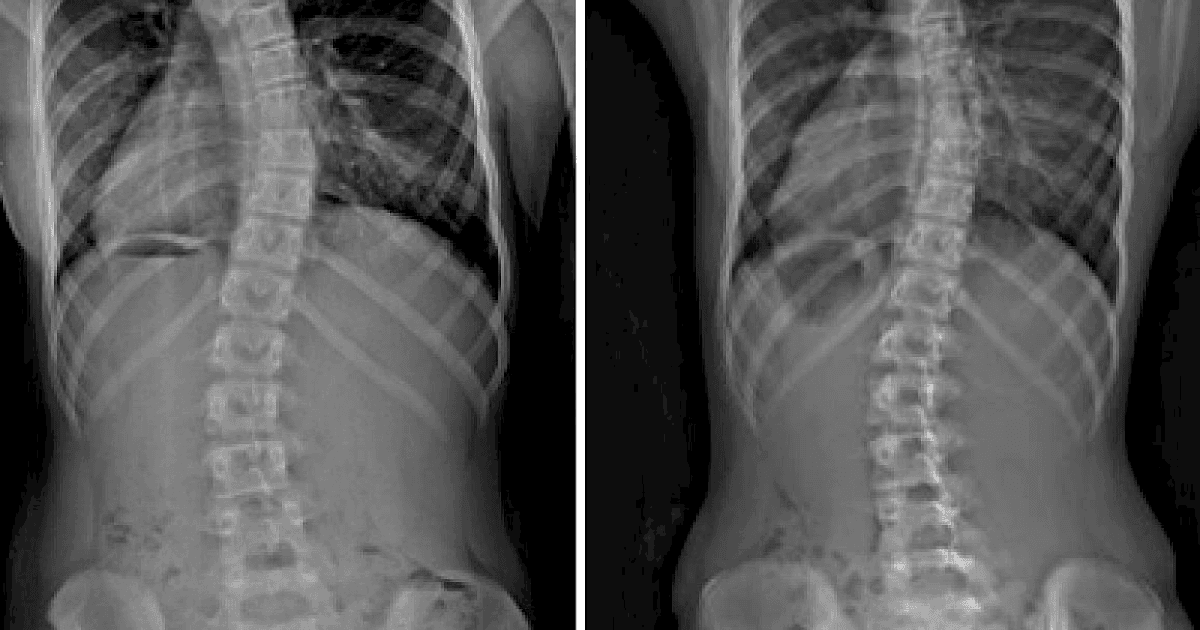

Lengkungan Tulang Belakang Kurva C dan S

Bentuk tulang skoliosis terdiri dari dua tipe yaitu kurva C dan S. Menurut Skoliosis My, skoliosis berbentuk huruf S atau ganda lebih kompleks, sedangkan berbentuk huruf C adalah bentuk skoliosis yang sederhana.

Baik bentuk skoliosis berbentuk S maupun berbentuk C, keduanya perlu mendapat perhatian, terutama selama masa pertumbuhan.

Selain itu, bentuk C yang berkembang dengan cepat dapat berubah menjadi skoliosis berbentuk S atau skoliosis ganda.

Lengkung skoliosis remaja dan dewasa yang berbentuk S memerlukan perhatian segera.

Bagaimana mengetahui skoliosis kurva S dan C? Ini diperlukan pemeriksaan radiologi untuk melihat rontgen tulang belakang dan melihat lebih jelas tentang bentuk dan derajat kelengkungan.

- Titik lokasi kurva S: Serviks, Toraks, dan Lumbal.

- Titik lokasi kurva C: Umumnya di thoracolumbal, tidak terkompensasi karena posisi asimetri.

Dokter biasanya akan meminta kamu untuk melakukan X-ray atau radiologi untuk memeriksa derajat kelengkungan yang disebut sebagai sudut Cobb.

Penting diketahui bahwa dalam mendiagnosis skoliosis, pengukuran sudut Cobb digunakan untuk menilai keparahan kelengkungan tulang belakang.

Berikut penjelasannya:

- Skoliosis Ringan: Sudut Cobb antara 10 hingga 25 derajat.

- Skoliosis Sedang: Sudut Cobb antara 25 hingga 40 derajat.

- Skoliosis Parah: Sudut Cobb lebih dari 40 derajat.

- Skoliosis Sangat Parah: Sudut Cobb lebih dari 80 derajat.